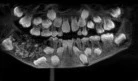

Los cirujanos indios que trataron a un paciente sospechando que había sufrido una intoxicación alimentaria quedaron atónitos cuando vieron que el origen de sus males eran las 263 monedas y 150 clavos que tenía en el estómago e intestinos, informa el periódico The Times of India.

El diario agrega a la lista de objetos ingeridos un trozo de correa de acero para perros, alfileres, una larga tira de metal, aguja de acolchar, metales puntiagudos y picos de hierro. La operación, realizada en el Hospital Sanjay Gandhi en la ciudad de Rewa (noreste del país), supuso la extracción de un poco más de 2 kilos de objetos del estómago del hombre.

El paciente de 32 años —a quien el periódico Daily Mail atribuye el nombre Maksud Khan— ingresó en el hospital con dolores abdominales. Se reporta que el hombre sufre problemas de salud mental. Sus familiares dicen que había entrado en una depresión y que es posible que a partir de ese momento empezara su adicción a comer objetos metálicos.

Los doctores han detallado que el paciente había estado comiendo metales durante un año, sin que nadie lo supiera. Han asegurado que habitualmente estos objetos no suponen ningún problema para la salud hasta que las partículas de metal comienzan a obstruir los intestinos.